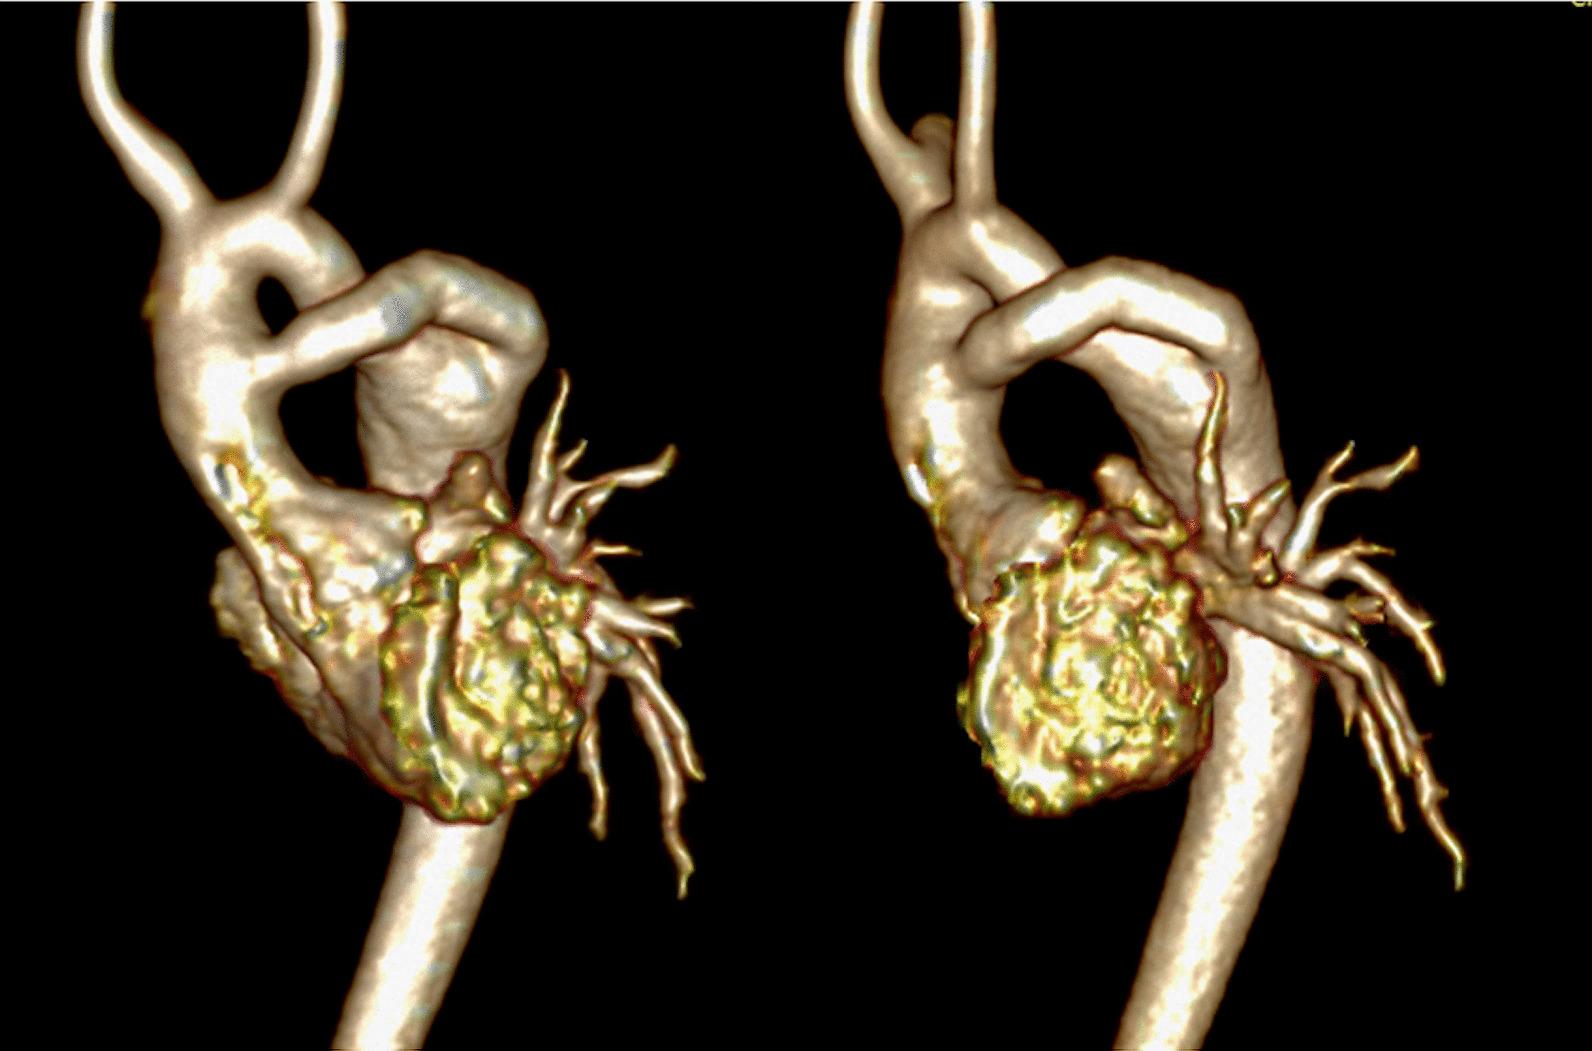

Cardiovascular magnetic resonance (CMR) has been utilized in the management and care of pediatric patients for nearly 40 years. It has evolved to become an invaluable tool in the assessment of the littlest of hearts for diagnosis, pre-interventional management and follow-up care. Although mentioned in a number of consensus and guidelines documents, an up-to-date, large, stand-alone guidance work for the use of CMR in pediatric congenital 36 and acquired 35 heart disease endorsed by numerous Societies involved in the care of these children is lacking. This guidelines document outlines the use of CMR in this patient population for a significant number of heart lesions in this age group and although admittedly, is not an exhaustive treatment, it does deal with an expansive list of many common clinical issues encountered in daily practice.

心血管磁共振(CMR)在儿科患者的管理和护理中已经应用了近 40 年。它已经发展成为评估最小的心脏的宝贵工具,用于诊断、介入前管理和随访。尽管在许多共识和指南文件中提到,但在儿科先天性心脏病和后天性心脏病领域,目前还缺乏一份由众多参与儿童护理的学会共同认可的、最新的、独立的、针对 CMR 使用的大型指南。本指南文件概述了 CMR 在该年龄段的许多心脏病变中的应用,尽管不能说是详尽的治疗方法,但它确实涉及了在日常实践中经常遇到的许多常见临床问题的广泛列表。